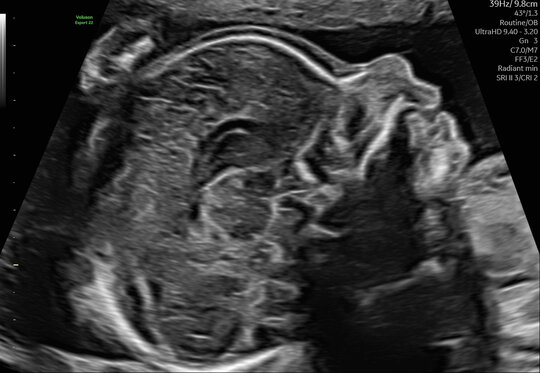

Kindliches Gesicht im Profil

Zahlreiche kindliche Erkrankungen lassen sich mittels einer weiterführenden Feindiagnostik mit hochauflösenden Ultraschallgeräten frühzeitig erkennen. Idealerweise wird diese Untersuchung zwischen der 20. und der 22. Schwangerschaftswoche durchgeführt. Zu diesem Zeitpunkt ist die Entwicklung aller Organe bereits weitgehend abgeschlossen. In unserer Pränataldiagnostik und Schwangerenambulanz wird eine solche Untersuchung von speziell geschultem und erfahrenem Personal durchgeführt.

Im Rahmen der Diagnostik untersuchen wir die kindlichen Organe wie das Herz und die Nieren, aber auch andere Strukturen wie etwa das Gehirn oder Gesicht zum Ausschluss einer Lippen-Kiefer-Gaumenspalte. Auch die Wirbelsäule mit der Fragestellung nach einem offenen Rücken oder die Knochen werden beurteilt.